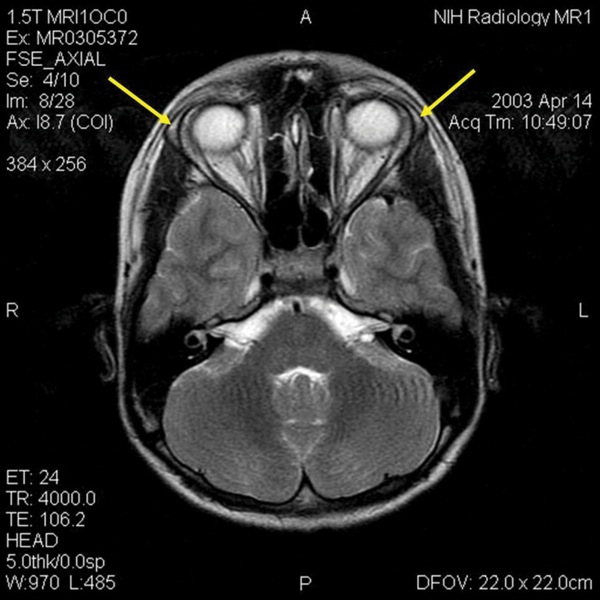

Diagnosis may be difficult, as symptomatology and genetic variations are variable. Allgrove syndrome usually appears in children whose symptoms include lack of tears, recurrent vomiting, dysphagia, severe hypoglycemia with seizures and shock. Neurologic changes such as ataxia, upper and lower motor neuron abnormalities, weakness, optic atrophy and mental retardation occur later.3 Genetic testing mutations have been identified but are variable. Triple A syndrome is caused by mutations in the AAAS gene, which encodes the protein ALADIN (for alacrima, achalasia, adrenal insufficiency, neurologic disorder) and the ACTH receptor genes.4 Several pathogenic variants of the AAAS gene have been described.5 The syndrome has been mapped to a 6-cM interval on human chromosome 12q13 near the type II keratin gene cluster.6